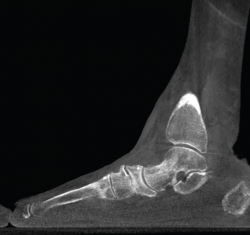

Articulación subtalar

La medición de las caras articulares anterior, media y posterior de la articulación subtalar se complica en un estudio simple radiográfico. La inclinación-orientación de las mismas en relación con la configuración del retropié y su implicación en el medio y antepié han sido estudiadas con la TAC en carga(8).

Figura 4. Estudio de la articulación subtalar bilateral.

- Patología y deformidad subtalares. Estudio de la configuración subtalar y artropatía de la misma (Figura 4).